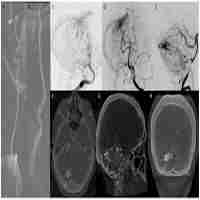

| Abstract | Background Spinal arteriovenous malformations in children are extremely rare and pose great risk for intraoperative hemorrhage. Congenital syphilis sometimes presents with vascular symptoms, however, there is little published on patients with a history of congenital syphilis presenting with spinal arteriovenous malformations. Case presentation A 15-month-old female with a history of congenital syphilis presented with urinary retention, fever, and subacute onset of paraplegia. MRI showed a lesion at T8-L1, angiogram was performed which confirmed the presence of a complex type IVc arteriovenous malformation and fistula from Artery of Adamkiewicz at L1-L2. It also showed peri medullary dilated veins and a pseudoaneurysm that compressed the spinal cord at T8-T10. Somatosensory evoked potentials and motor-evoked potentials were not recordable on the bilateral lower extremities prior to surgery. Once the patient was optimized for surgery, osteoplastic laminotomies from T6-T12 were performed. The dura was opened and the intradural, intramesenchymal hematoma was evacuated. There were two episodes of brisk arterial bleeding with hypotension during resection of the hematoma. The patient was taken to the angiography suite from the OR to successfully coil the large aneurysm. Intraoperative spinal cord monitoring remained undetectable in the bilateral lower extremities. The patient’s paraplegia remained unchanged from preoperative presentation. Conclusion Congenital syphilis may present with vascular changes that might impact surgical approaches and treatment outcomes in patients with spinal arteriovenous malformations. Preparation for massive transfusion and intraoperative monitoring are imperative in ensuring a safe perioperative experience. |